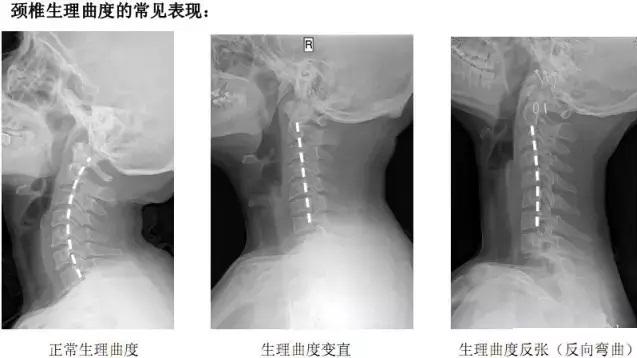

其实,人体颈椎有一个生理曲度,各个椎体后缘形成一个连续光滑的曲线。但是,有的人因为长时间不正确的坐姿,长时间的劳累,颈椎缺少活动、脊柱损伤生理曲度,就会导致颈部生理弯曲变直,严重的甚至反曲,生理曲度就被破坏了。枕啤酒瓶治颈椎在某种程度上好似是契合生理曲度,对颈椎有一定的帮助,但因为啤酒瓶置于颈椎下方, 并不完全符合生理曲度可能会对颈椎造成伤害,且脊椎病复杂,所以并不建议用此方法治疗颈椎病。